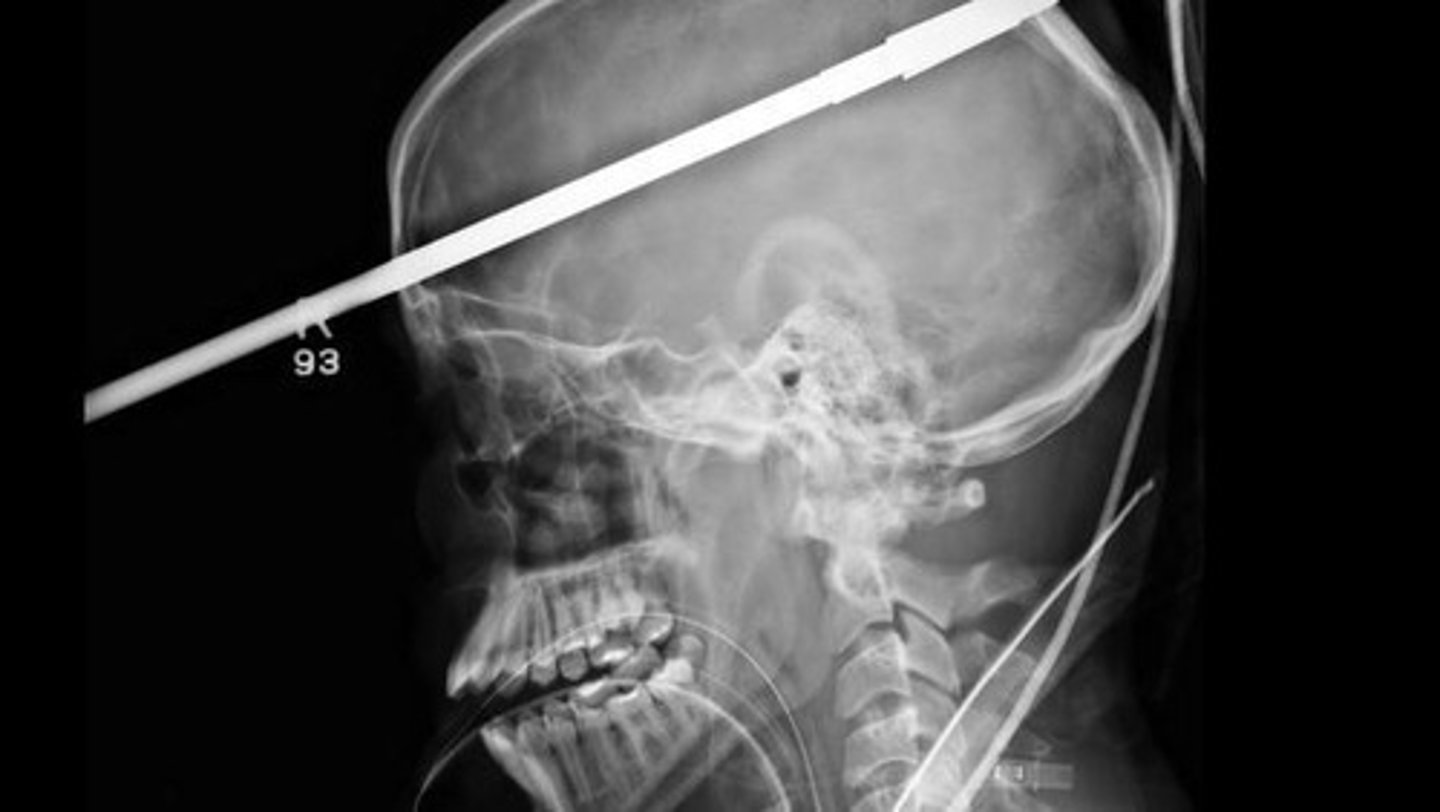

What is a penetrating head injury?

An injury where brain tissue is damaged by an object that has pierced the skull.